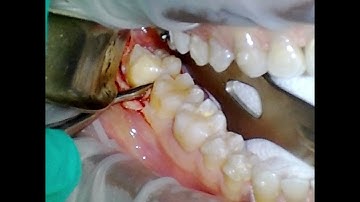

Erupted Wisdom Tooth Extraction